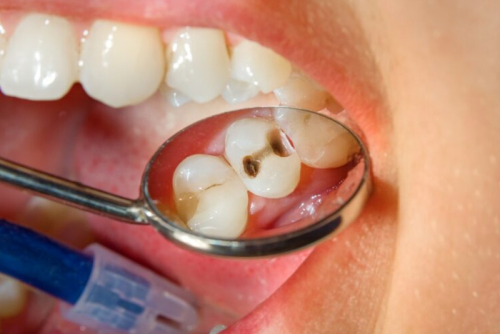

- Sâu răng: Răng khôn mọc lệch có thể tạo ra môi trường thuận lợi cho vi khuẩn phát triển, từ đó dẫn đến sâu răng.

- Bệnh nướu răng: Khó khăn trong việc vệ sinh đúng cách có thể là nguyên nhân gây viêm nướu, tạo điều kiện cho các bệnh lý răng miệng khác phát triển.

- Viêm quanh thân răng: Tình trạng viêm nhiễm có thể xảy ra khi răng khôn mọc lệch không đủ không gian, tạo áp lực lên các răng xung quanh.